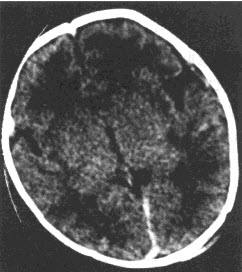

- 单项选择题患儿,女,15天,吸吮反射减弱,CT检查如下图,最可能的诊断为()

B、新生儿缺氧缺血性脑病

- B